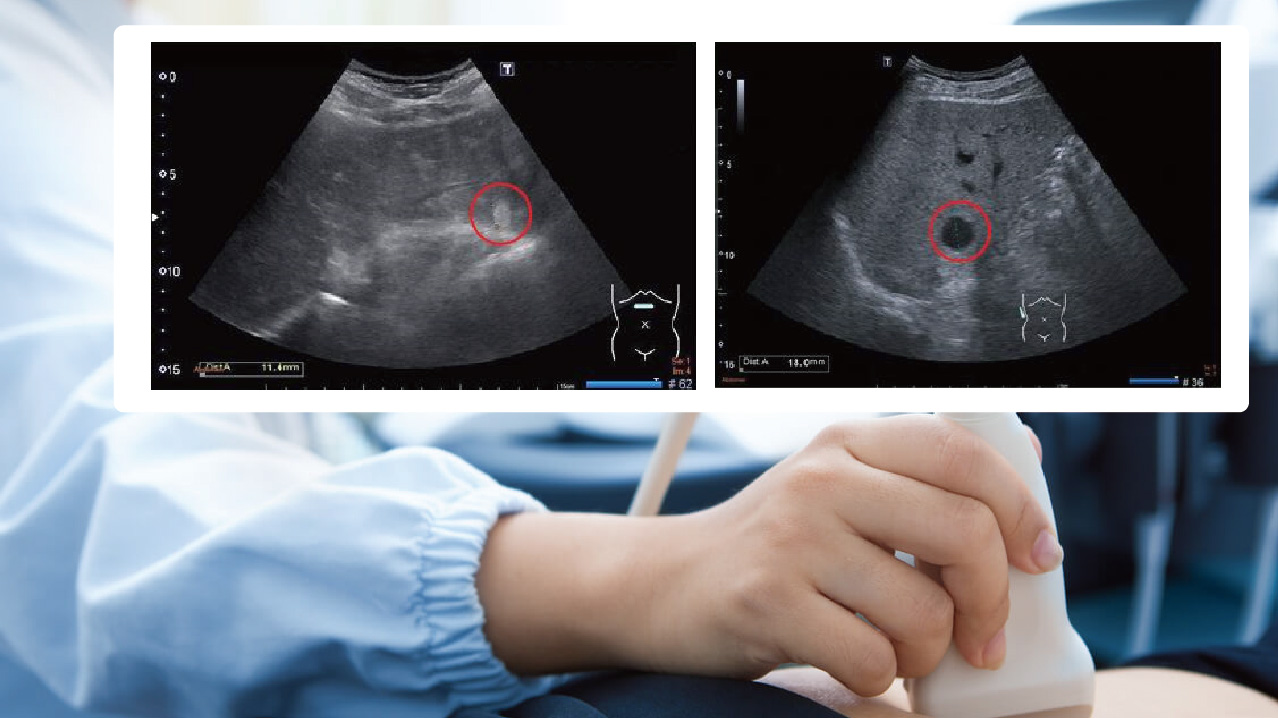

1.肝囊腫

就是常說的水泡,是一個含清澈液體的囊狀結構,囊腫可很大也可以很小,通常毫無症狀且不影響肝臟功能,也無藥物可讓肝臟囊腫消失。特別大的水泡有可能壓迫周邊器官產生症狀。隨著年紀增長,囊腫數目可能會增加或有變大的跡象,很小的水泡也有可能被吸收消失,患者不必緊張擔心,只要定期追蹤和平相處即可

2.血管瘤

是血管異常增生而形成的腫瘤,發生率大約在2-5%之間,能否發現有賴檢查醫師的細心觀察,大部分的血管瘤呈現高回音影像,也就是影像上屬於較白的成像,確診血管瘤最好是在不同的觀察切面都能看到影像。由於小血管瘤沒有症狀也不會影起肝臟功能的變化,因此只需定期追蹤大小變化即可,極少數的血管瘤會緩慢長大。對於無法確認性質或有長大的跡象,可安排腹部電腦斷層或核磁共振攝影來鑑別診斷。